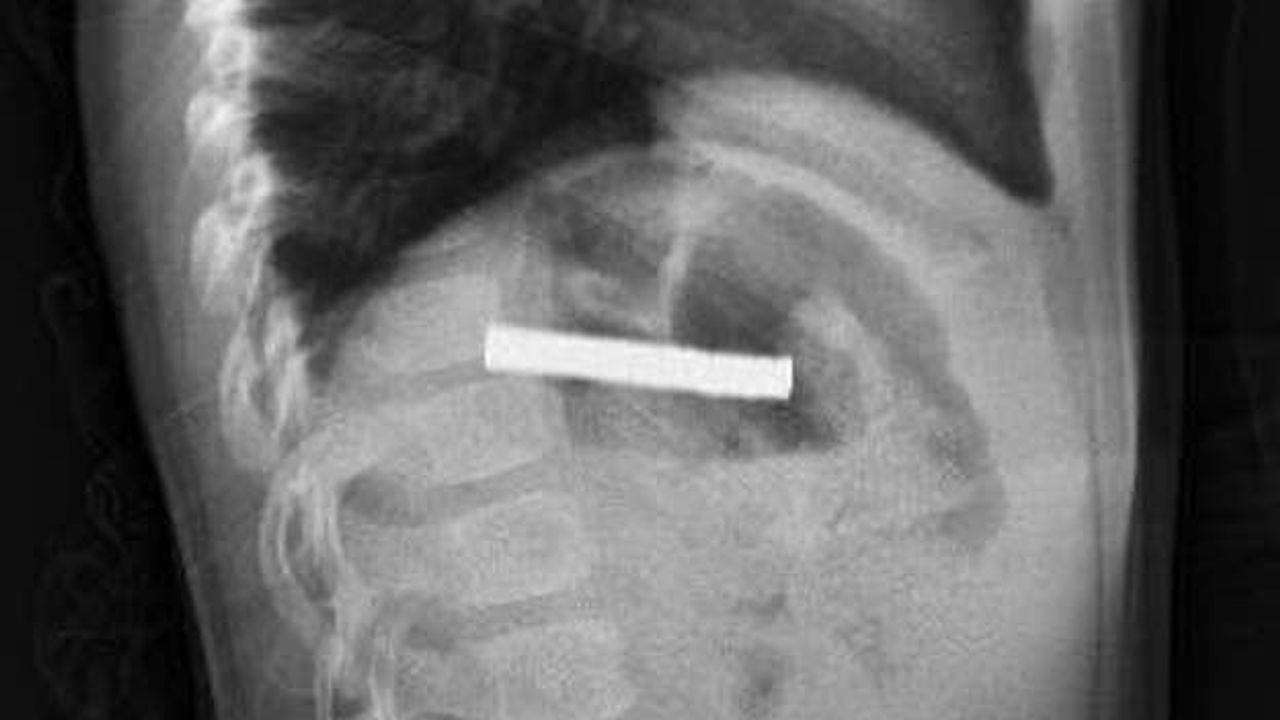

Edinilen bilgilere göre, Erzurum’da yaşayan 3 yaşındaki çocuk, evde oynarken 19 adet küçük mıknatısı yuttu. Kısa süre sonra rahatsızlanan çocuk, ailesi tarafından hastaneye götürüldü. İlk müdahalenin ardından durumun ciddiyeti fark edilince küçük hasta Elazığ’daki Fırat Üniversitesi Hastanesine sevk edildi.

Fırat Üniversitesi Çocuk Gastroenteroloji Hepatoloji ve Beslenme Bilim Dalı Başkanı Prof. Dr. Yaşar Doğan, hastayı acilen ameliyata aldı. Yapılan endoskopik işlemle çocuğun yemek borusuna ve mide girişine yapışan 19 mıknatıs başarılı şekilde çıkarıldı.